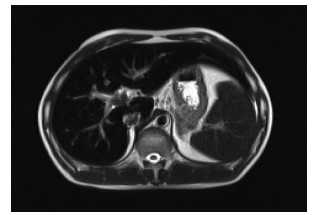

A case of splenic arteriovenous fistula with abdominal pain and gastrointestinal bleeding as the first symptoms

Yuanyuan CAI, Zhongwen WU, Juan LU

2021, 37(5): 1186-1188. DOI: 10.3969/j.issn.1001-5256.2021.05.043

Abstract(1011) HTML (291) PDF (2876KB)(49)

Abstract: